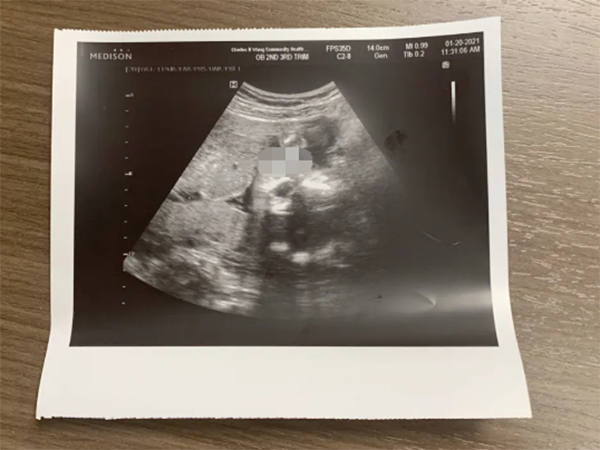

健康增长的重要指标胎儿体重是评估胎儿生长状况的关键指标之一,在第22周的产检中,医生通常会通过超声波检查来测量胎儿的体重,正常情况下,第22周胎儿的体重应该约为约430克(15盎司)左右,需要注意的是,每个胎儿的体重增长速度可能会有所不同,因此医生会根据个体差异来评估是否在正常范围内。

器官发育的指标除了体重,医生还会测量胎儿的头围和腹围,头围是指胎儿头部周围的尺寸,腹围是指胎儿腹部周围的尺寸,这些指标可以反映出胎儿头部和腹部器官的发育情况,在第22周产检中,正常的头围应该约为18.1厘米(7.2英寸),腹围应该约为19.4厘米(7.6英寸),医生会结合这些数据来评估胎儿器官的正常发育情况。

保护和支持胎儿的重要液体羊水是孕妇子宫中的液体环境,对于保护和支持胎儿的发育至关重要,在第22周产检中,医生会通过超声波检查来评估羊水的量,正常情况下,第22周胎儿的羊水量应该在正常范围内,通常被描述为“正常”或“充足”,过多或过少的羊水都可能会与胎儿发育问题相关,因此医生会密切关注羊水量的变化。

胎儿心脏健康的指示器胎心率是评估胎儿心脏健康的重要指标之一,在第22周产检中,医生会使用多普勒仪器来监测胎儿的心跳频率,正常情况下,第22周胎儿的胎心率应该稳定在120-160次/分钟的范围内,不规则的心跳频率可能是心脏问题的迹象,因此医生会注意观察胎心率是否正常。